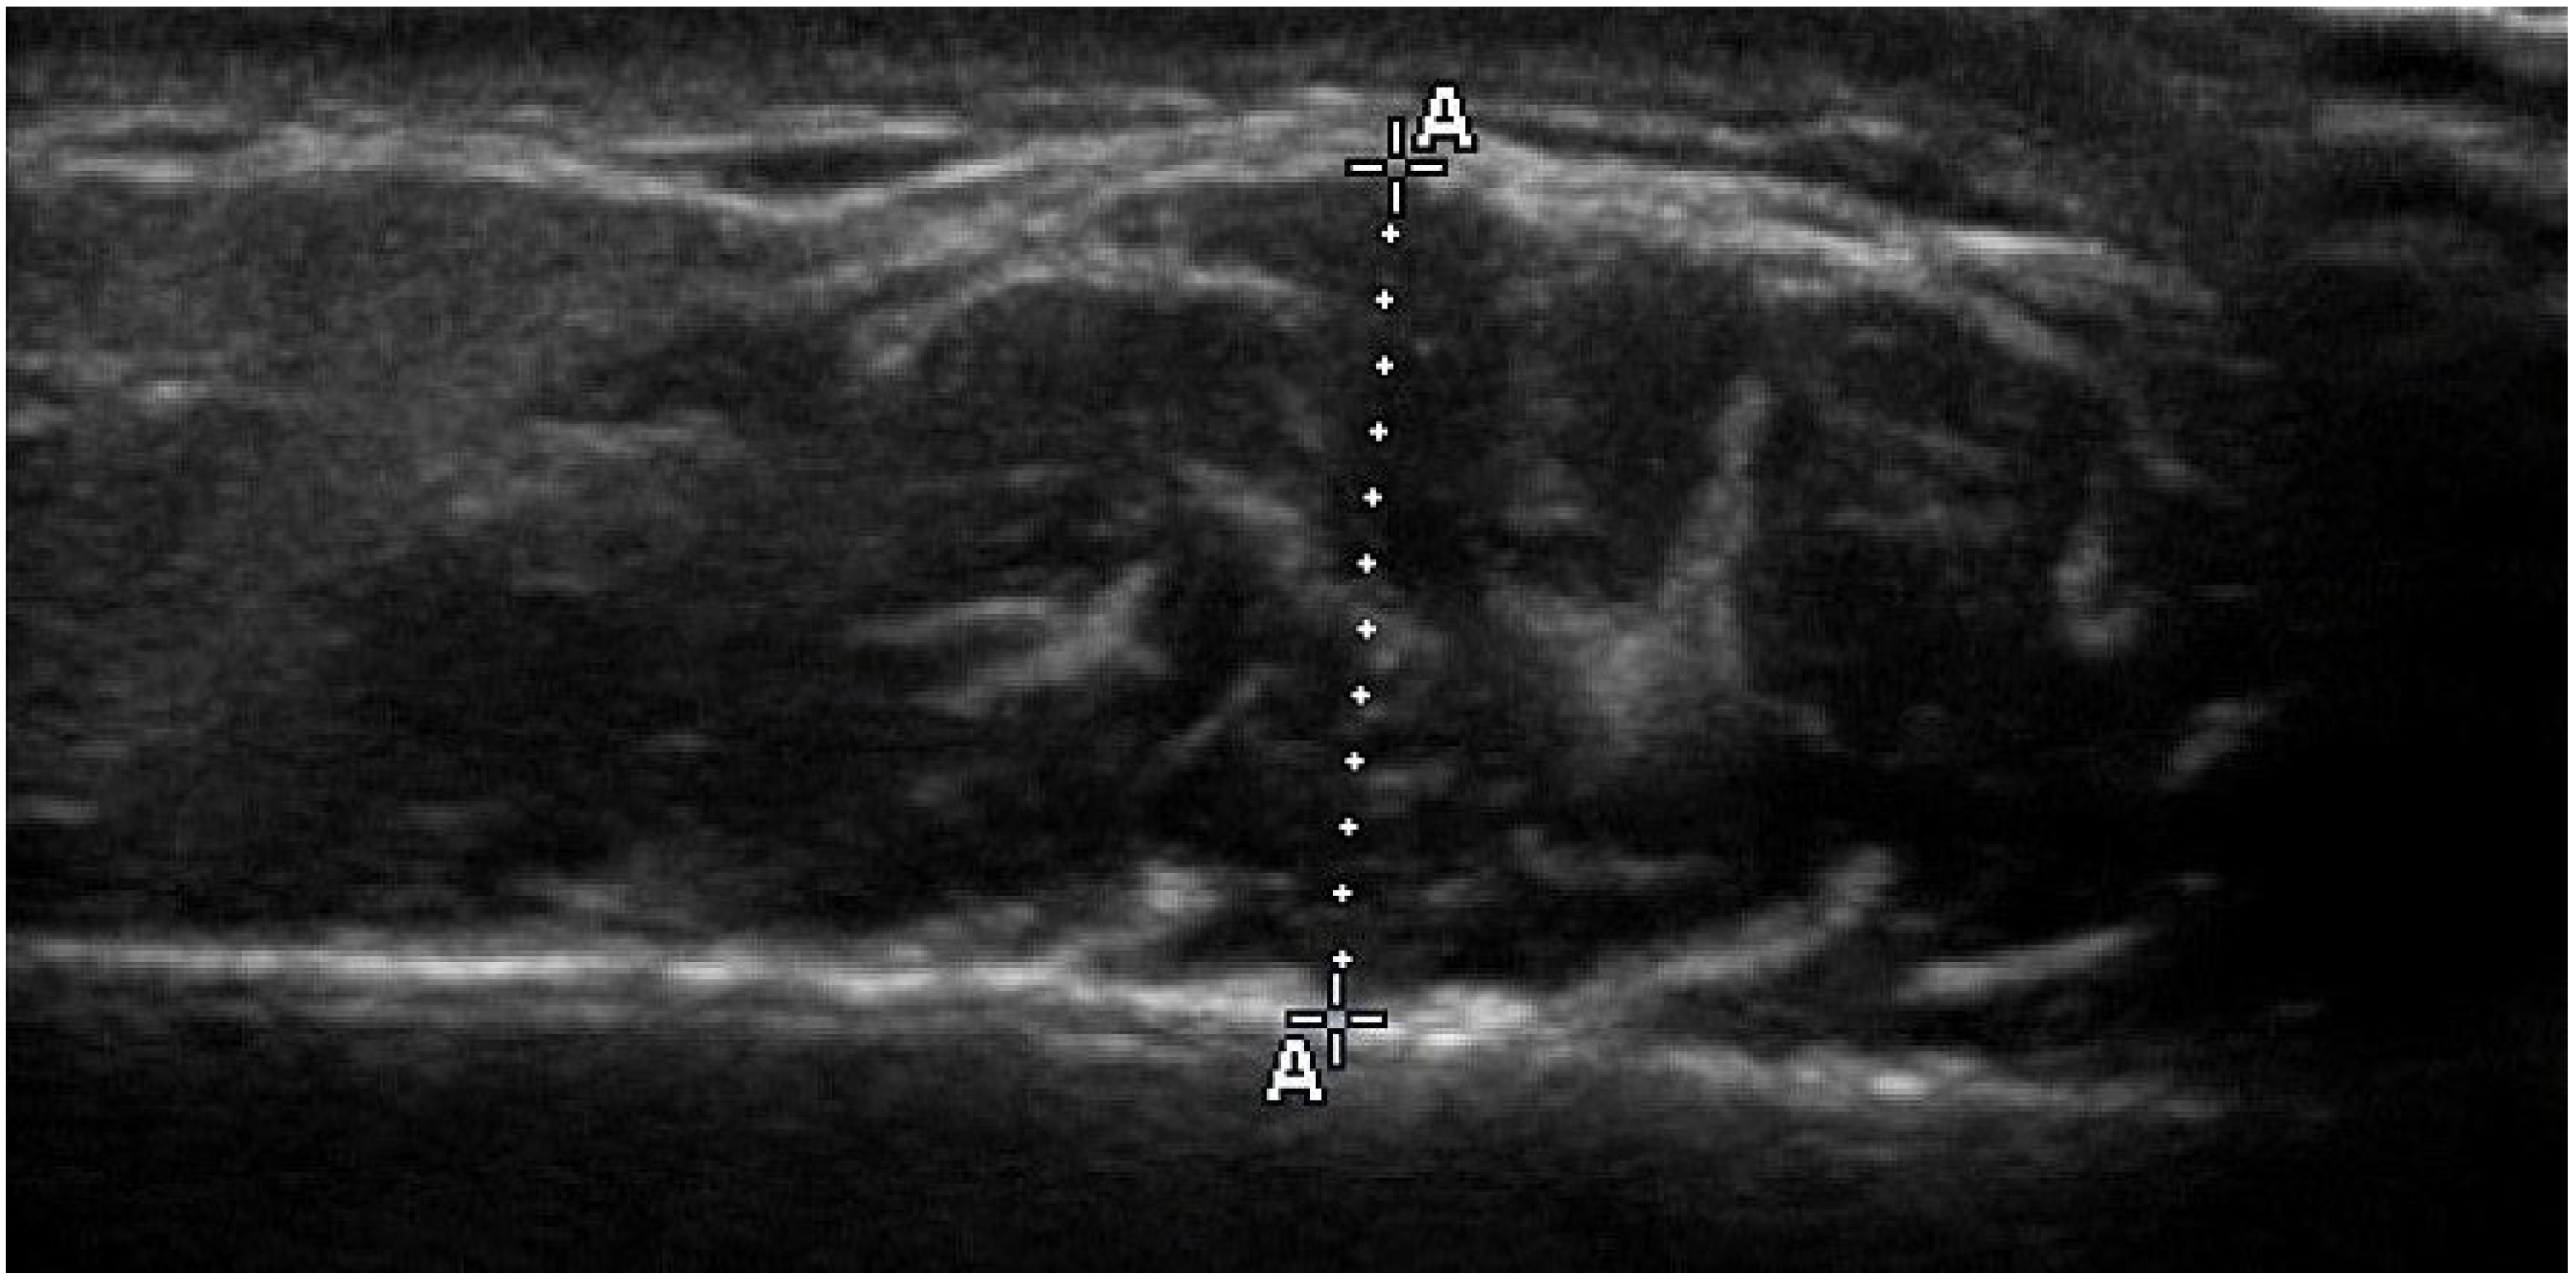

2.4. Ultrasonographic Thickness of Masseter Muscle